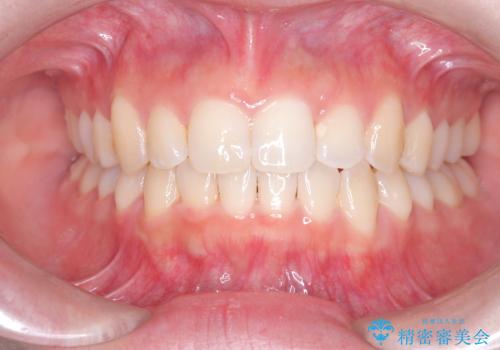

前歯の逆の咬み合わせを、目立たない矯正でスムーズに改善

- 右上の前歯(2番)が下の歯より内側に入っている反対咬合を主訴にご来院されました。精密な検査の結果、この反対咬合を解消するためには、右上の歯列に前歯を出すためのスペースを確保する必要があると判明しました。患者様のご希望に合わせ、透明で目立たないインビザライン(マウスピース矯正)による治療計画を立案。奥歯全体を奥へ動かす遠心移動でスペースを作り、反対咬合を解消することを目指します。

今回の矯正治療では、透明なマウスピース型の装置インビザラインを使用しました。治療は、緻密なデジタル計画に基づき、奥歯から順に歯列全体を後方へ移動させる遠心移動を実施し、前歯を前に出すためのスペースを確保しました。このスペースを利用して、内側に入り込んでいた右上2番をスムーズに前方に誘導し、正常な咬み合わせへと改善。目立たないインビザラインで、機能的な咬み合わせと美しい前歯の並びを獲得していただけました。